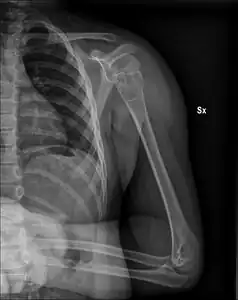

| X-ray: Simple bone cyst in left upper arm of 13 year old | |

Unprovoked break in the long bone of the upper arm,, with "fallen leaf" sign. -